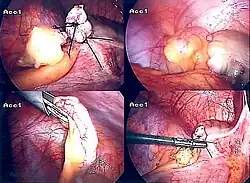

Диагностическая лапароскопия показана в сомнительных случаях, может переходить в лечебную лапароскопию при технической возможности, когда имеются условия для лапароскопической аппендэктомии; требуется письменное согласие пациента на удаление червеобразного отростка.

Постановка диагноза острого аппендицита является показанием к проведению экстренного оперативного лечения. При отсутствии явлений разлитого перитонита используется доступ Макбурнея (McBurney), иногда называемый в отечественной литературе доступом Волковича-Дьяконова. Основной этап операции при остром аппендиците — аппендэктомия (удаление червеобразного отростка).